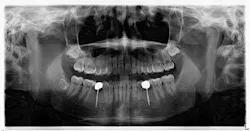

To begin with, there was, without argument, adequate space present for traditional, wider-based platform implants in these sites. So why were mini implants used? As it was understood by the parents, it was the newest technology and standard of care. Their concerns of function, tooth replacement, esthetics, and financial burden were addressed (it was done on trade). This conveys an important point — patients have relatively simple expectations, and when met, they are happy.

Longevity and function. Premolars don’t get the brunt of mastication forces, but they definitely get their fair share. If the occlusal forces are not centered over the implant just right, then we observe a first-class type of lever that can cause long-term stability issues. It could be argued by some that the 20 mm implant length could render a certain amount of support, but again, the aforementioned point must be referenced — there is/was adequate space for wider based platform implants to be placed.